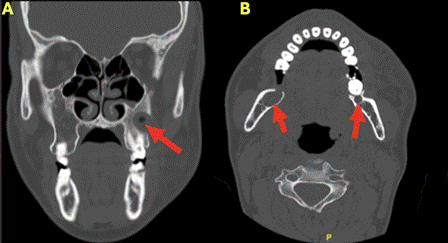

The patient presented again in August 2024 due to an episode of left hemifacial volume increase, which was managed in the emergency department of another hospital. Antibiotic treatment and drainage of the purulent content were performed. Maxillofacial computed tomography (CT) revealed three hypodense cystic lesions: one in the left posterior hemimaxillary region, corresponding to the recurrence of an OKC previously treated in 2021, and two located at both mandibular angles (Figure 2). Biopsy results confirmed the diagnosis of OKCs. Therefore, enucleation with peripheral osteotomy was performed for the smaller mandibular lesions, along with MCS application, and cannulation of the maxillary lesion for decompression followed by enucleation.

Figure 2. CT scan taken in the Emergency Department showing three hypodense lesions marked with a red arrow. (A) Hypodense cystic lesion in the left maxillary area, superinfected and corresponding to the recurrence of the lesion treated in 2021. (B) Hypodense cystic lesions at both mandibular angles, lesions that were not present in 2021.